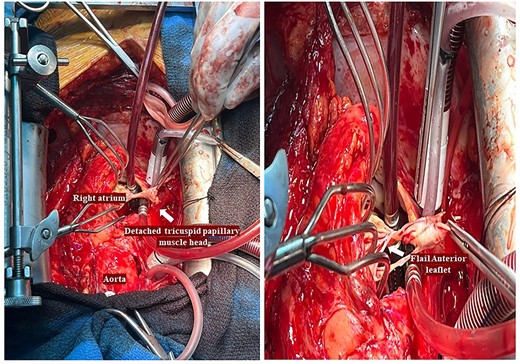

He had a redo-median sternotomy. Cardiopulmonary bypass was instituted through aortic cannulation connected to the bypass machine via a bifurcated arterial line along with the femoral ECMO cannula. The SVC and IVC were cannulated before opening the right atrium. The TV was inspected which revealed a flail anterior leaflet, attached to the ruptured head of the papillary muscle (Fig. 3).

Intraoperative pictures demonstrating a flail anterior leaflet attached to the ruptured head of the papillary muscle.